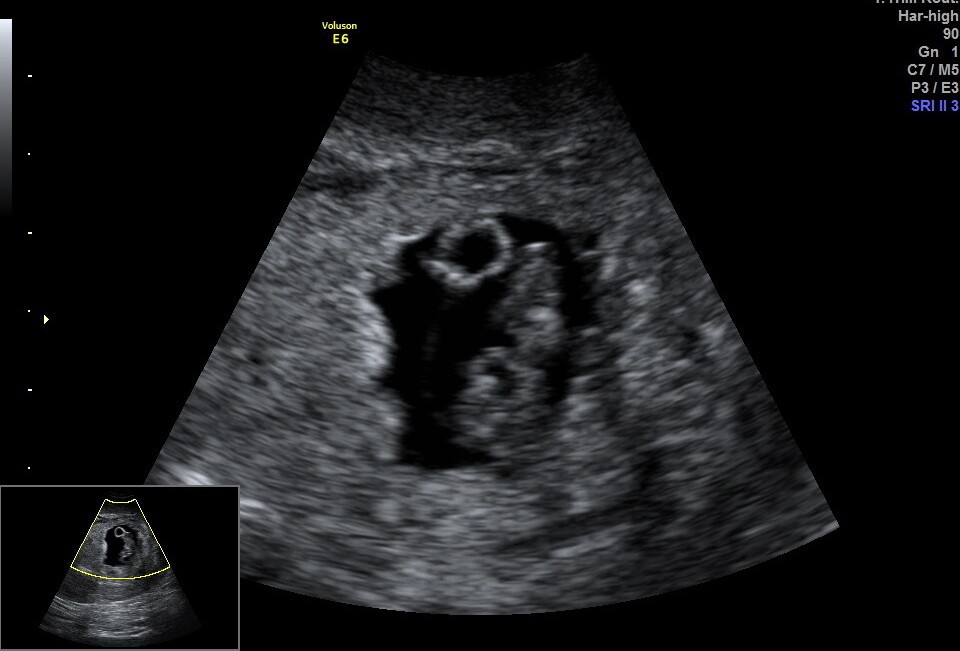

Poniżej zdjęcie z wczorajszego USG (7+4), serduszko pięknie bije.

Czy u Was też to ciałko żółte jest wciąż widoczne? Pytałam lekarza i powiedział, że na tym etapie to jest ok.